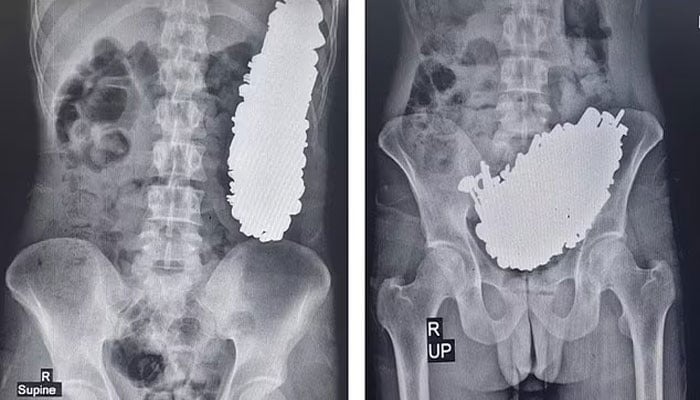

ایرانی ڈاکٹروں نے 37 سالہ شخص کے معدے سے 452 دھاتی اشیاء نکال لیں۔ یہ چیزیں چابیاں، کنکر، سکریوز اور دھاتی نٹ وغیرہ تھے جو اس نے نگل لیے تھے۔

کیس کی تفصیل کے مطابق مریض کو پیٹ میں شدید درد تھا۔ وہ مسلسل الٹیاں کر رہا تھا اور کچھ کھانے پینے کے قابل نہ تھا۔ جب ایکسرے کیا گیا تو معلوم ہوا کہ اس کے پیٹ میں دھاتی چیزوں کا ڈھیر جمع ہے۔ اس وجہ سے نظام اخراج کا راستہ بھی بلاک ہو گیا تھا۔ سرجری کے ذریعے اس کے معدے سے 452 دھاتی اشیاء نکال لی گئیں۔ ان کا وزن تین کلو گرام کے قریب تھا۔ ڈاکٹروں کے مطابق وہ کم از کم تین ماہ سے یہ چیزیں کھا رہا تھا۔

ڈاکٹروں نے اس بات کی وضاحت نہیں کی کہ وہ ایسا کیوں کر رہا تھا۔ تاہم انہوں نے نوٹ کیا کہ وہ افیون کا سخت عادی تھا۔ آپریشن کے تین دن بعد اس میں سائیکوسس کی تشخیص ہوئی۔ اس مرض میں فرد حقیقت کی دنیا سے دور کی کیفیت میں ہوتا ہے۔ ڈپریشن، سر کی چوٹ، دماغ میں رسولی اور منشیات کا استعمال اس کا سبب بن سکتے ہیں۔

ماہرین نے دھاتی چیزیں کھانے کے سلسلے میں کوئی اصطلاح استعمال نہیں کی۔ تاہم غیر خوردنی اشیاء کھانے کو طبی اصطلاح میں پیکا کہا جاتا ہے۔ اس کیس کی تفصیل جرنل آف میڈیکل کیس رپورٹس میں شائع ہوئی ہے۔